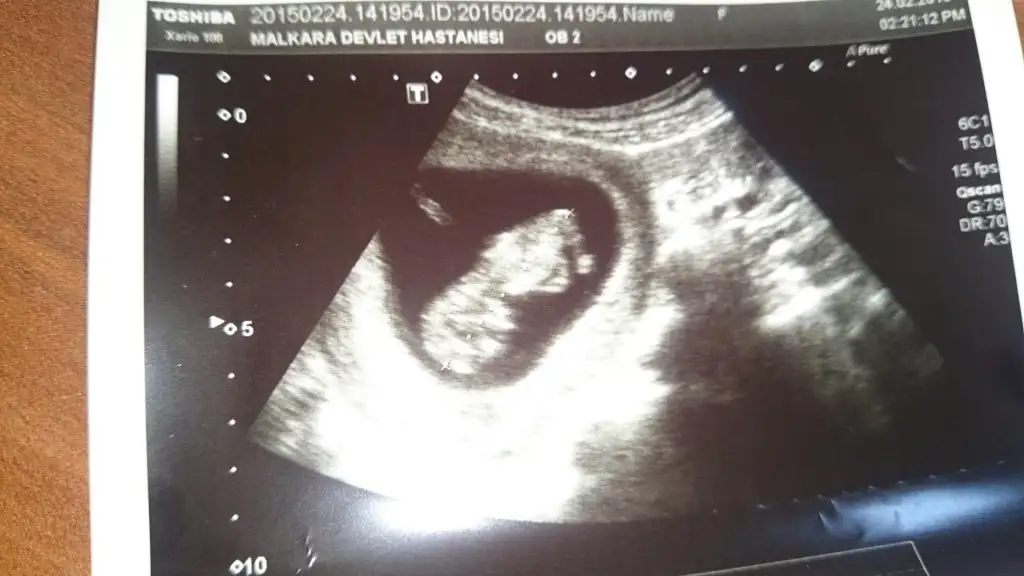

Kızlar 11+4 nolur yorum yapın çok mrk ediyorum

• DSC_0979.webp

DSC_0979.webp

27,9 KB · Görüntüleme: 90